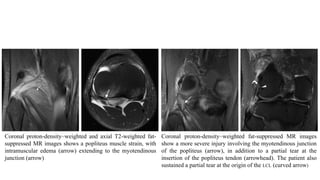

Coronal proton-density–weighted and axial T2-weighted fat-

suppressed MR images shows a popliteus muscle strain, with

intramuscular edema (arrow) extending to the myotendinous

junction (arrow)

Coronal proton-density–weighted fat-suppressed MR images

show a more severe injury involving the myotendinous junction

of the popliteus (arrow), in addition to a partial tear at the

insertion of the popliteus tendon (arrowhead). The patient also

sustained a partial tear at the origin of the LCL (curved arrow)